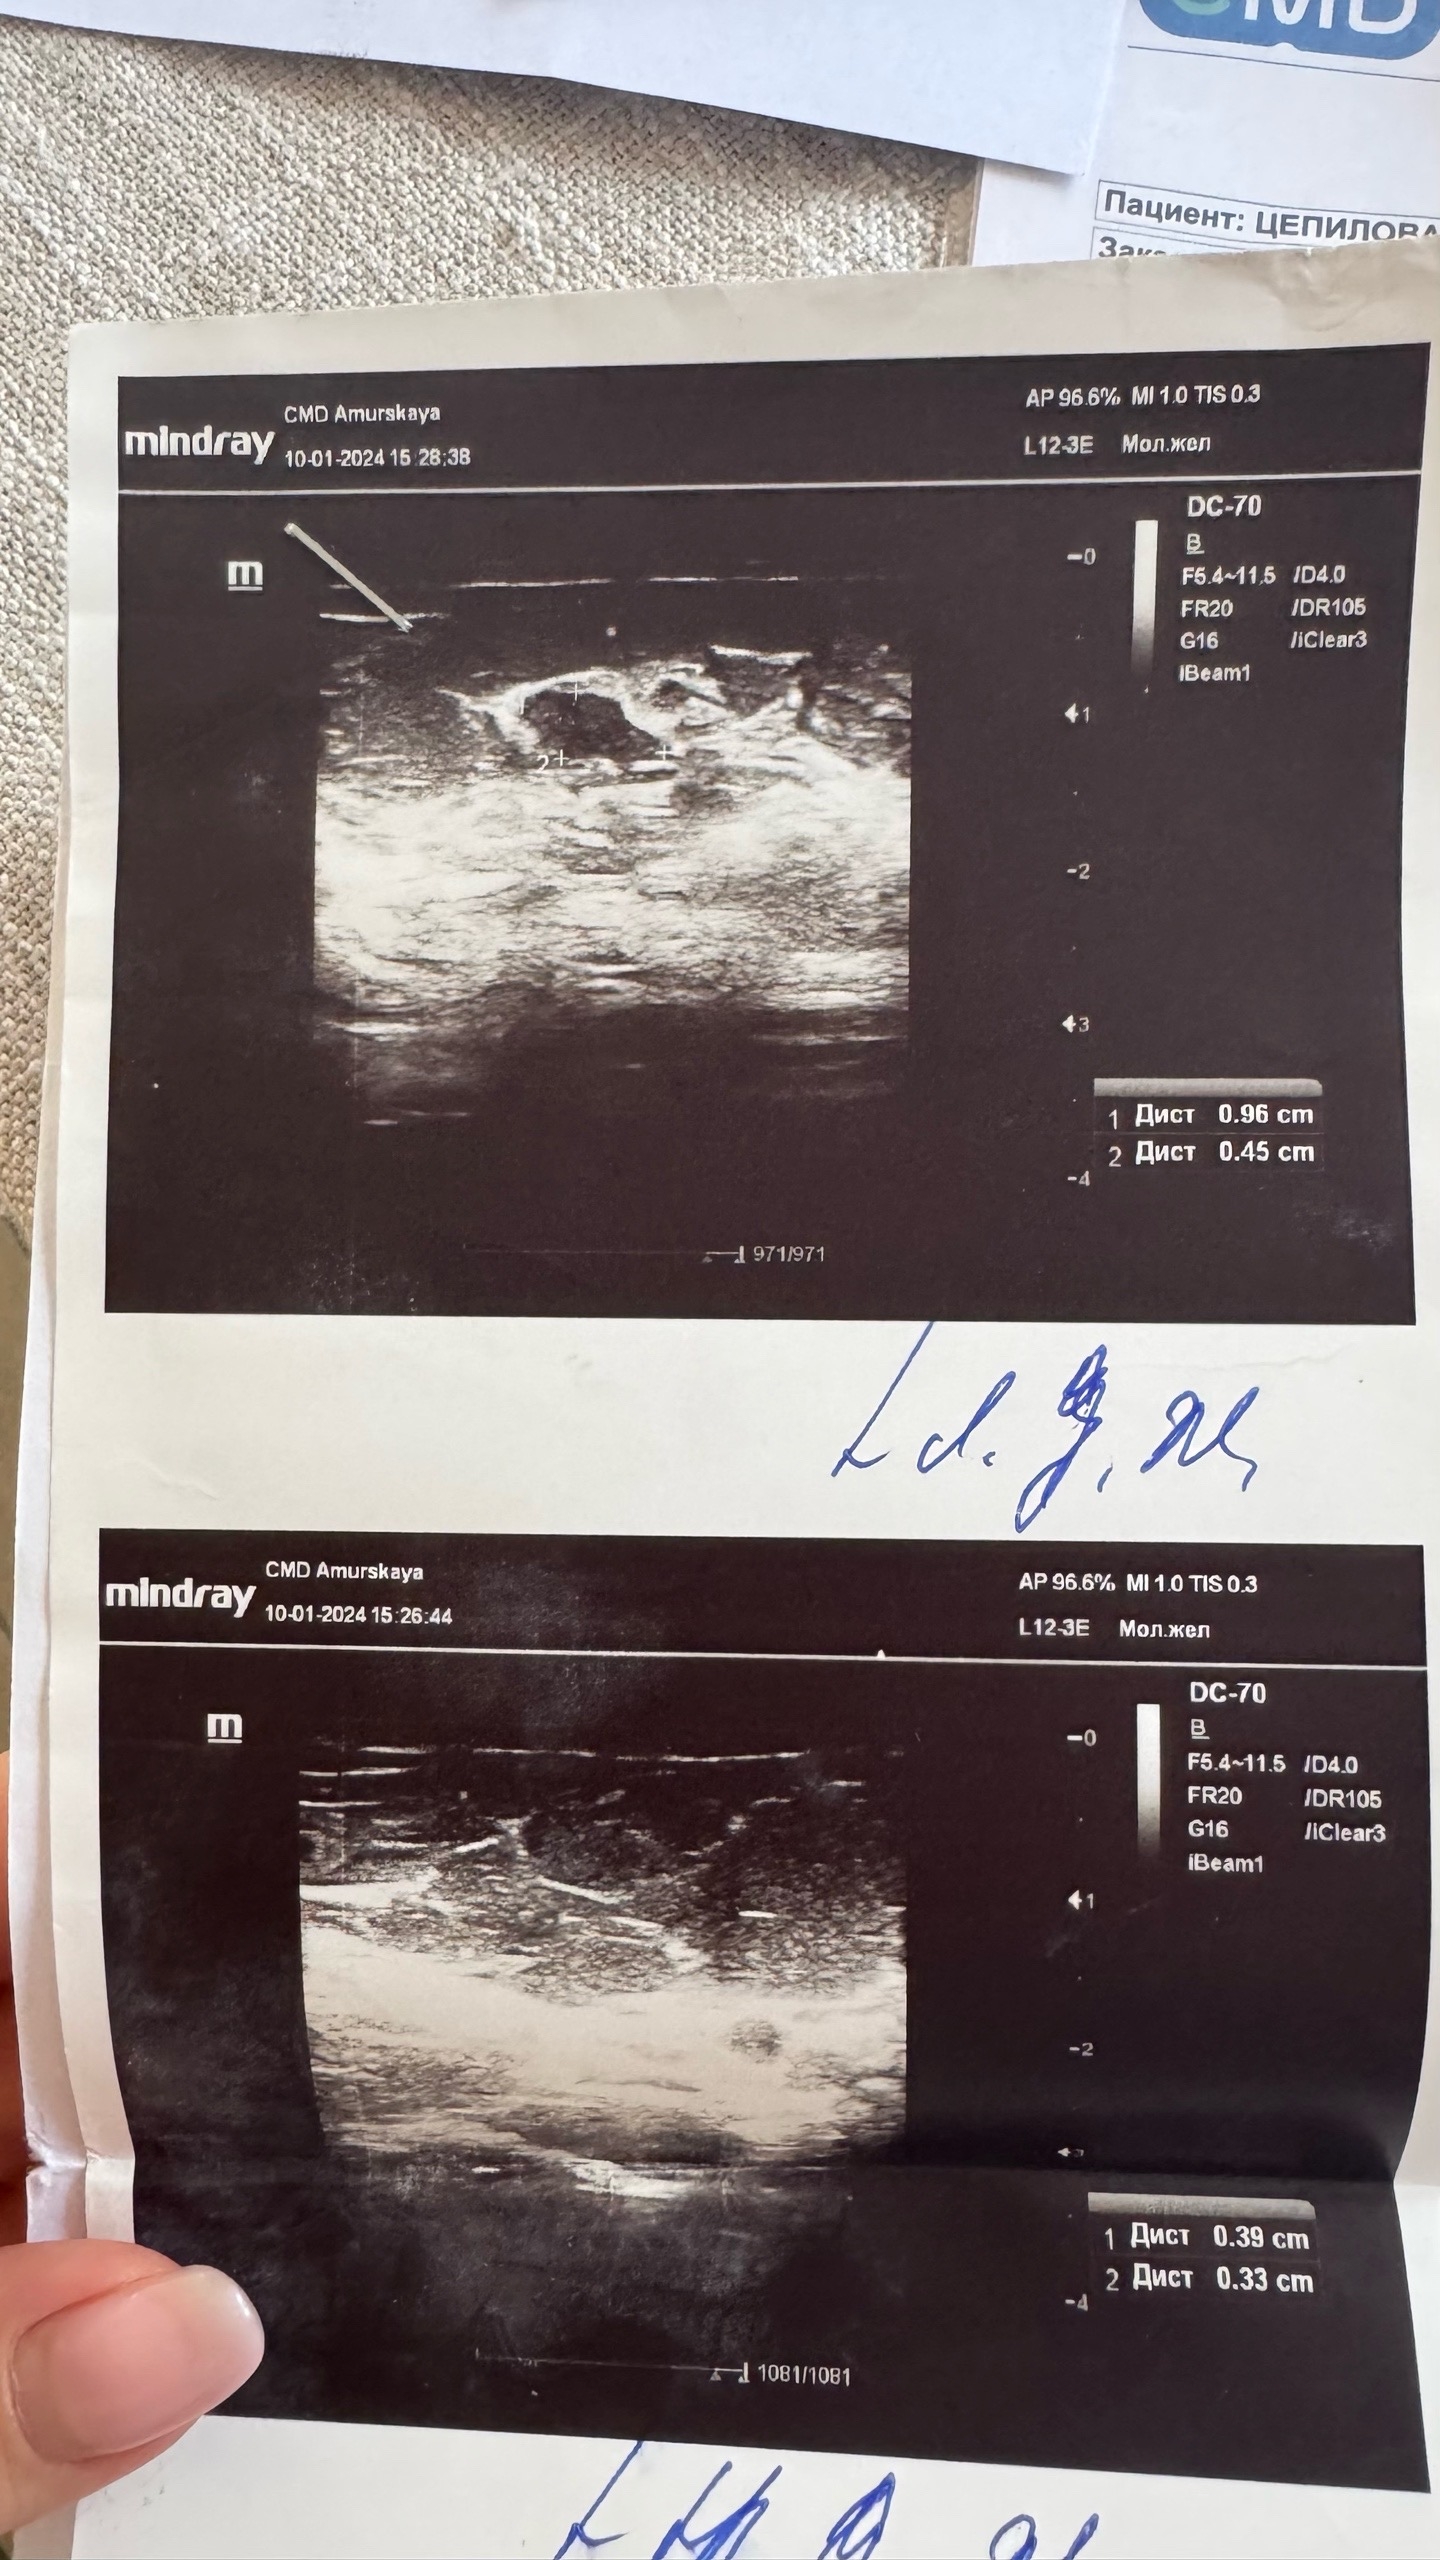

Январь 2024. В 2024 году (мне было 32) вновь пошла на узи молочных желез и на узи обнаружилось образование в левой мж "гипоэхогенное неправильной овальной формы 9,6*4,5*9,6 с четкими неровными контурами, аваскулярное". В заключении — фиброаденома? атипичная киста? под вопросом. BIRADS не написали (тогда я еще не знала о том, что узист должен присваивать уровень по этой классификации).

На плановом узи мне сообщают, что нужно сходить к онкологу. Ставят BIRADS 3 (предположительно доброкачественно) и в заключении пишут, что 2 образования аналогичных размеров. Я пугаюсь и начинаю пересматривать старые заключения узи и выясняю, что уже на двух последних узи у меня было 2 образования, но я ввиду частого посещения врача уже не сильно внимательно просматривала результат, слишком опрометчиво доверяя врачам. Мне ничего не говорили и я не вчитывалась. Меня окутал липкий страх, так как я поняла, что за полгода у меня выросло образование в 1 см.